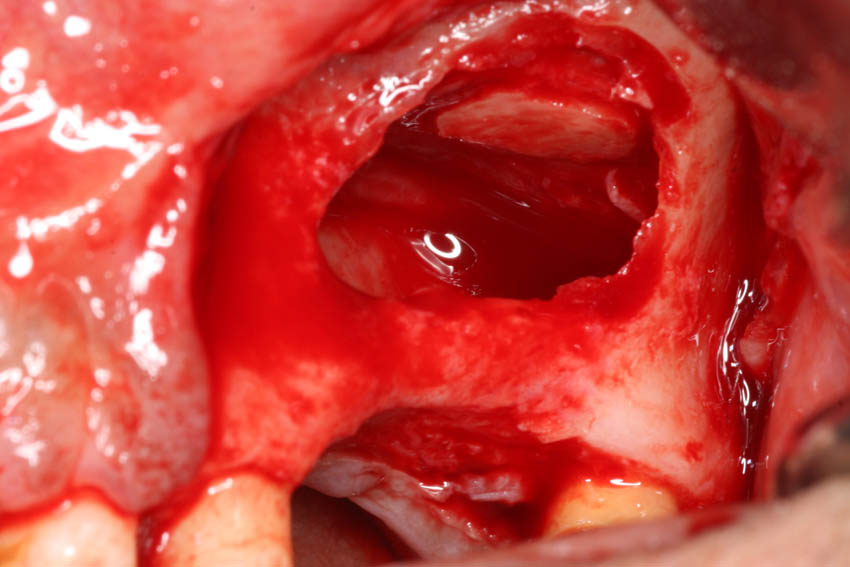

→ Ανύψωση του εδάφους του ιγμορείου με τη μέθοδο του οστικού παραθύρου.

→ Λήψη μοσχεύματος αυτογενούς οστικού μπλοκ από τον κλάδο.

→ Τεχνική διχασμού της φατνιακής ακρολοφίας για τη διεύρυνση του εύρους της.

→ Λήψη οστικών κόκκων αυτογενούς οστικού μοσχεύματος.

→ Ατραυματική εξαγωγή δοντιών με τα πιεζοηλεκτρικά άκρα σχήματος συνδεσμοτόμου.